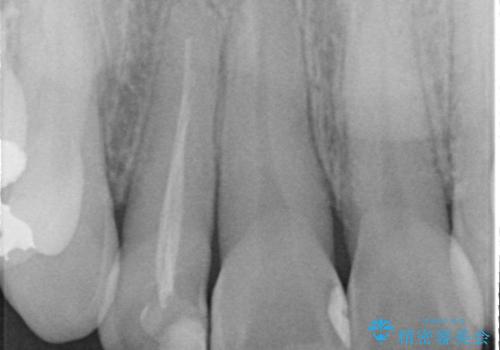

- 「前歯の見た目が気になる」を主訴に来院された患者様です。

失活歯による歯の変色とCR(コンポジットレジン)の劣化による審美不良でした。

オールセラミッククラウンで治療し見た目の改善を行いました。

まず劣化したCRと虫歯を除去した後、仮歯に置き換えました。歯のマージンラインを綺麗に削り光沢が出るまで研磨した後にオールセラミッククラウンの型取りを行っています。